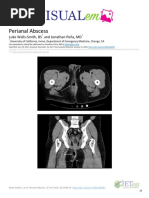

Perianal abscess

Fig 1 Possible sites of anorectal (“perianal”) abscesses

Fig 2 Typical clinical appearance of a superficial perianal abscess